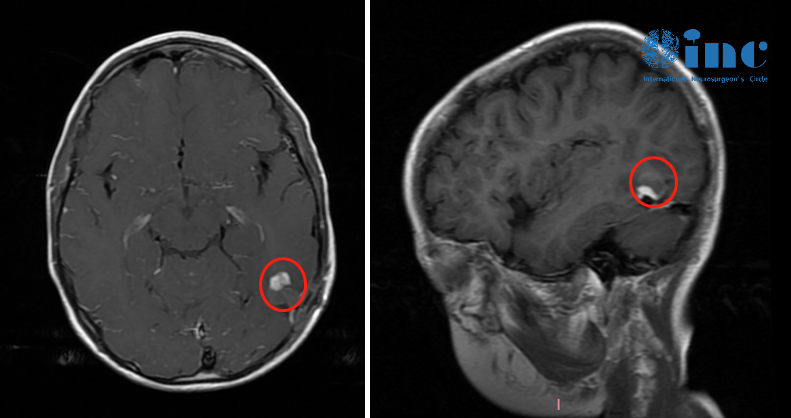

2020年,4歲的安安因反復(fù)嘔吐、嗜睡,引起了媽媽的警覺。在父母的陪伴下,安安就診當?shù)蒯t(yī)院兒科,但是檢查結(jié)果顯示孩子一切正常。一年后,安安再次出現(xiàn)嘔吐后愣神,伴頭及雙眼向右偏,這是癲癇發(fā)作的表現(xiàn)。頭顱MRI檢查提示左顳下回團塊狀異常信號,可能為海綿狀血管瘤。

很快,安安接受了癲癇病灶切除術(shù),術(shù)后病理結(jié)果顯示為兒童型彌漫性低級別膠質(zhì)瘤(WHO II級)。然而,時間到了2022年,在一次常規(guī)復(fù)查時,安安的腫瘤竟然復(fù)發(fā)了。